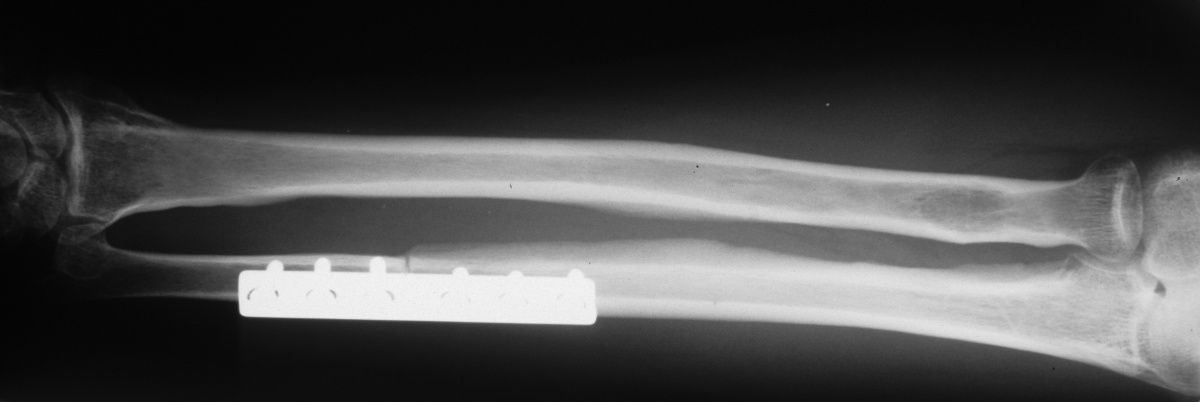

| Uneventful healing. Final

supination was 45 degrees. |